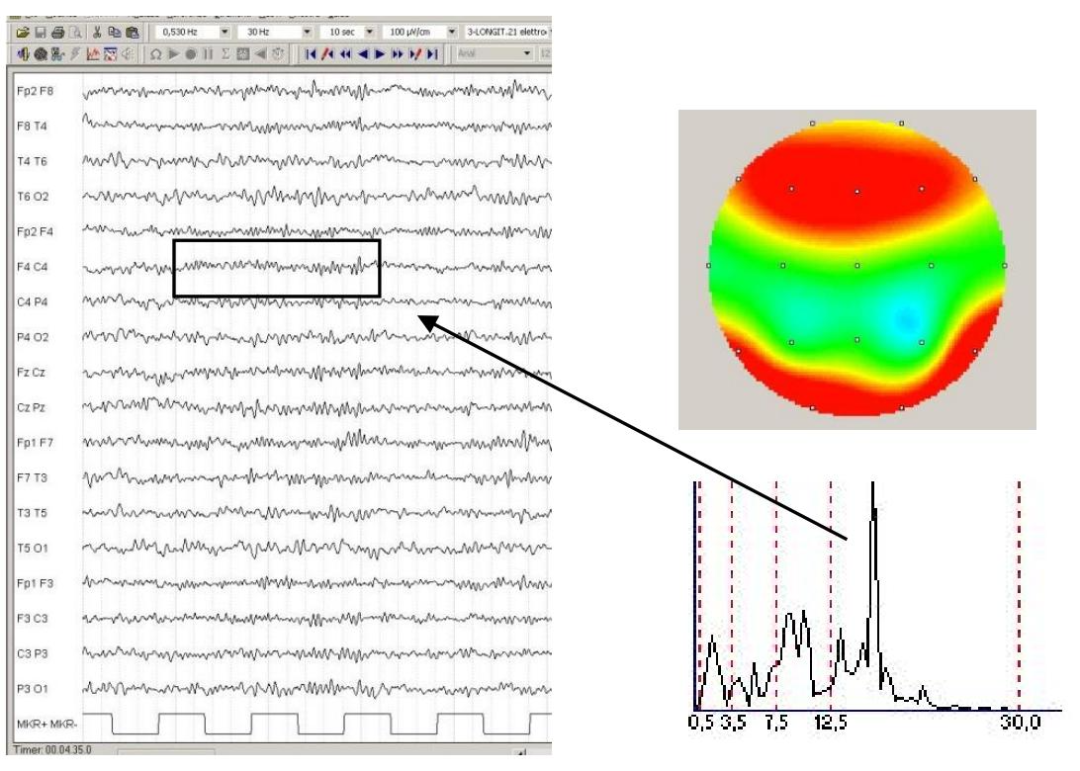

EEG信号特征

波形:EEG 信号波形多样,常见形态包括正弦波(如α波)尖波(如癫痫放电)和棘波(如局灶性异常)。根据脑电波沿基线偏转的次数分为:单相波、双相波和三相波;根据波形分为:正弦样波、多形性波、弓形波(梳状波)、棘波、尖波;由2个或2个以上相连续的波组成复合波:棘慢复合波、尖慢复合波、多棘波、多棘慢复合波等。

电压:范围通常为10-100μV,振幅受神经元排列方向(如锥体细胞垂直皮层表面)及同步化程度影响,大小反映了信号的强度。

重复频率:由神经元集群振荡的周期性决定,不同频率的信号与大脑的不同状态和功能相关,例如α波的8-13 Hz频率与丘脑-皮层回路的节律性活动相关。

空间分布:不同频段节律具有脑区特异性,如α波在枕叶优势分布,β波在感觉运动区活跃。

出现方式(节律性、连续性、同步性、对称性):正常的α节律具有明显的节律性呈现规则的正弦波形态;而异常脑电图可能会出现节律紊乱的情况。连续性方面,正常脑电图的背景活动一般具有一定的连续性,若出现中断或异常的间歇,则可能是异常表现。同步性指不同脑区的EEG信号在时间上的一致性,如α节律在双侧半球通常具有较好的同步性;对称性则是指EEG信号在双侧大脑半球对应区域的相似程度,正常情况下,双侧半球的EEG信号在频率、振幅和波形等方面应基本对称,若出现不对称,可能提示存在神经系统疾病。

脑电节律的时域特征

δ(0.1 - 4Hz):高振幅(>100μV),宽基底正弦波,周期长达250-2000 ms

θ(4 - 8Hz):中等振幅(20-100μV),规则正弦波,常以短程爆发形式出现

α(8 - 13Hz):纺锤形调幅正弦波,振幅10-50 μV,闭眼时枕区显著增强

β(13 - 30Hz):低振幅(<20 μV),快速振荡,常叠加于慢波之上

以及γ(30 - 80Hz):极低振幅(<10μV),高频振荡,需高采样率设备捕捉及癫痫研究中的高频振荡(HFOs,>80Hz):极短时程(<10 ms),低振幅振荡,常与癫痫样放电共存。

波形持续时间:棘波(<70 ms)与尖波(70-200 ms)的区分对癫痫诊断至关重要;睡眠纺锤波持续0.5-2秒,是N2期睡眠的标志。